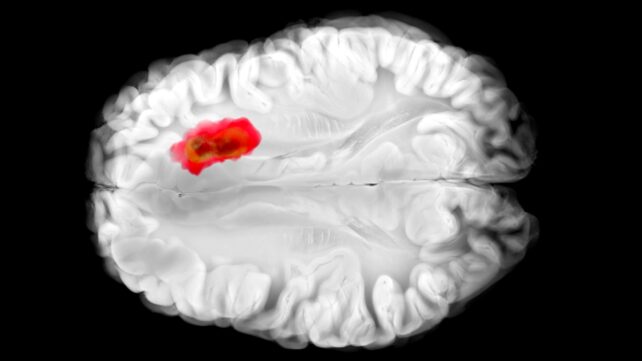

That same enzyme, as it happens, is thought to play a role in aggressive glioblastoma brain cancers. This new understanding of hydralazine could lead the way to new cancer treatments, as well as improve the drug's effectiveness for its current targets.

Previous studies have shown that glioblastoma tumors are often high in ADO, hijacking it to produce a chemical called hypotaurine, which helps the cancer cells spread, survive for longer, and tolerate stress.

Hydralazine effectively mutes ADO, the team found: RGS proteins aren't attacked, blood vessels aren't squeezed, and blood pressure drops. In experiments with human glioblastoma cells, hydralazine halted tumor growth by blocking ADO.